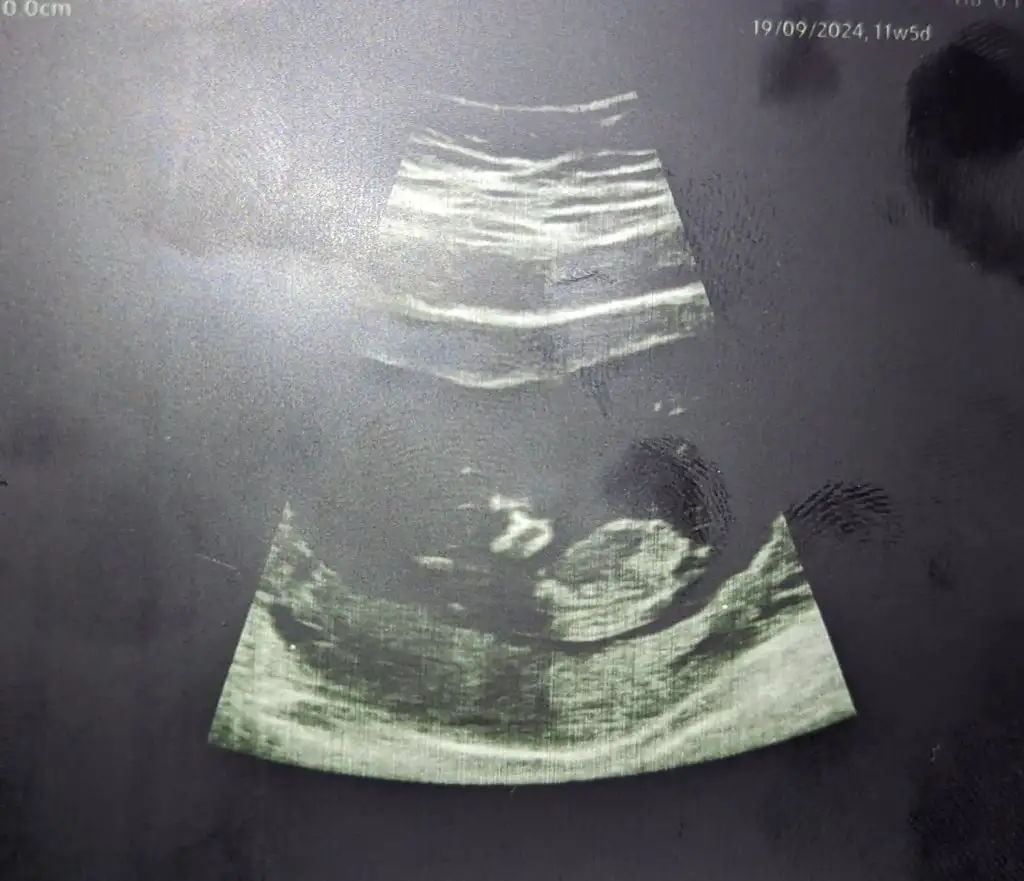

Merhaba arkadaşlar biliyorum erken ama sabırsızlanıyorum aranızda tecrübeli ve bilgili anneler vardır. 12 haftalığız bugün perinatolog kız olduğunu söyledi geçen hafta da kendi doktorum erkek olduğunu söylemişti. İkisi de %90 ihtimal diye beni çok ümitlendirdi siz ne düşünüyorsunuz farklı zamanlardaki görüntülerini ekliyorum yardımcı olan herkese cookkkk teşekkürler